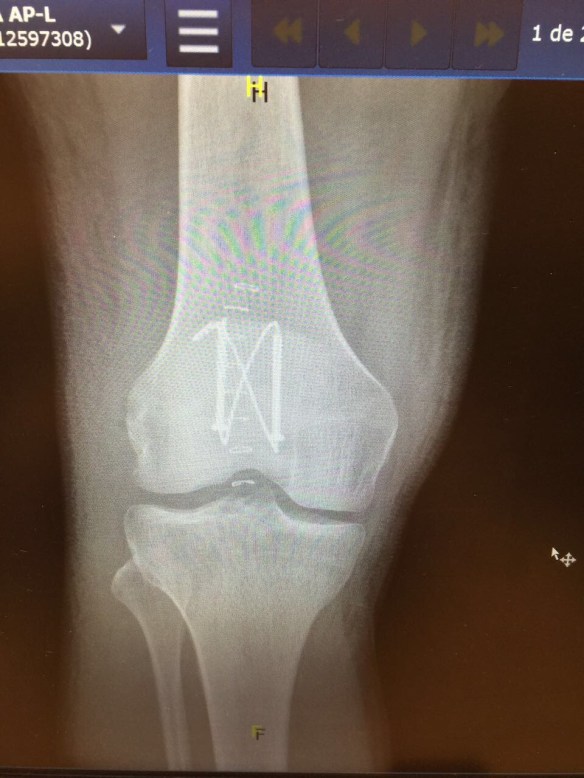

Även om jag kände att något var riktigt knasigt direkt när jag föll hade jag ändå hoppet uppe under röntgen att inget skulle vara skadat, att luxation skulle vara diagnosen och att det därför skulle gå att rätta till knäskålen så att den hamnade på rätt plats igen. Röntgenplåten talade dock sitt tydliga språk; Horisontell patellafraktur, frakturerad i huvudsakligen två delar, men med en undre del som krossats aningen mer.

Det förklarade varför jag låg där på båren och inte kunde röra benet. Förutom att givetvis smärtan var olidlig vid förflyttning fanns det inte längre någon kontakt mellan lårets muskler och smalbenet som möjliggjorde flexion. Detta är också anledningen varför en sådan här fraktur inte går att lösa på något annat sätt än med en akut operation.